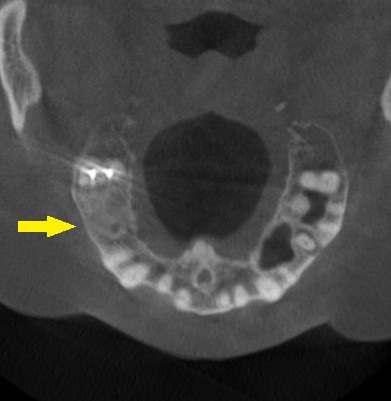

CTを撮影してみると、骨の高さが3mm程しかありませんでした。

そこで、ワイド径のインプラントを使用して、骨造成術を回避する方法を提案させていただきました。

これならと同意いただけましたので、本日、直径6mm、長さ7mmのインプラントを人工骨を用いることなく埋入しました。

下の写真、2段目が手術前、3段目が手術後のCTです。